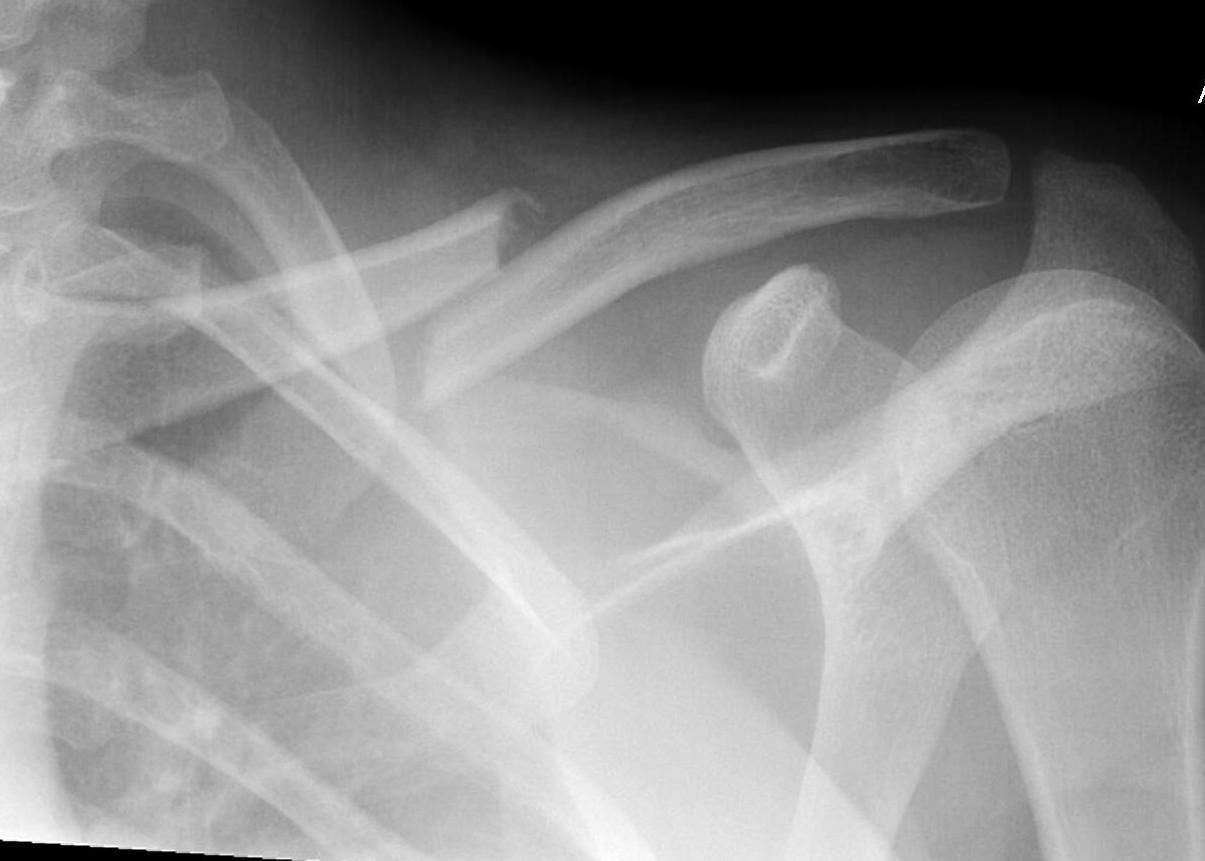

Xray

Shortening

Displacement

- the proximal fragment elevated by sternocleidomastoid

- lateral fragment sags down with weight of shoulder

Compound clavicle fracture

Shorted / displaced midshaft clavicle fractures

Z shaped midshaft clavicle fracture